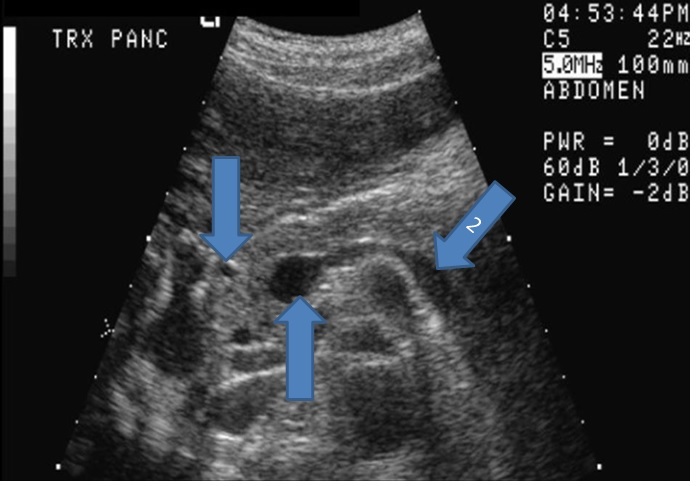

Q

From the left to right label the structures

A

1. Gastroduodenal artery this is in the head of the pancreas

2. Porta of confluence

3. Splenic vein